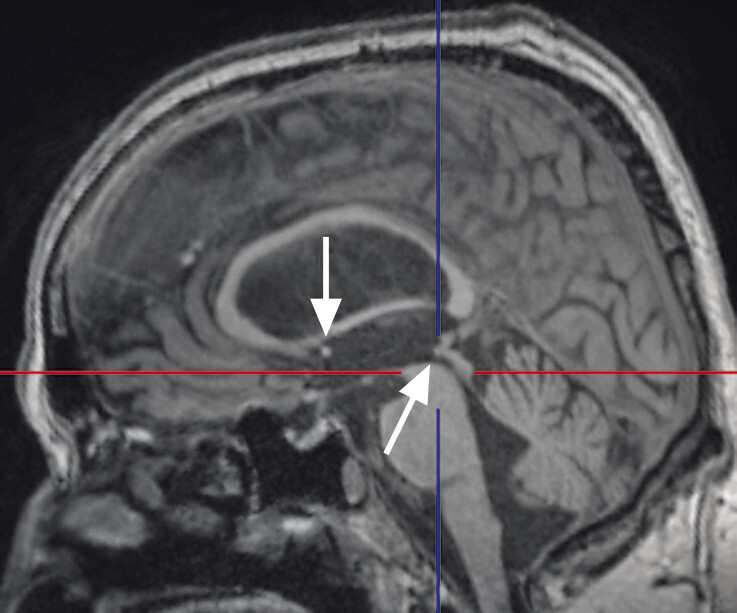

Abb. 69.9 Parkinson-Syndrome: Differenzialdiagnose progressive supranukleäre Parese mit Richardson-Syndrom.

62-jähriger Mann mit über 3 Jahre zunehmender Bewegungsverlangsamung und unsicherem Gangbild. Die MP-RAGE-Aufnahmen zeigen eine deutliche Mittelhirnatrophie mit Kolibri- (a) und Mickey-Mouse-Zeichen (b). Das Mittelhirn/Pons-Verhältnis liegt mit 0,15 im pathologischen Bereich (Normalwert ca. 0,24). Die voxel- und regionenbasierte morphometrische Analyse (c) zeigt neben der Mittelhirnatrophie eine links-frontomesial betonte Atrophie, das FDG-PET (e) einen Hypometabolismus dieser Regionen. Dieses Muster ist typisch für eine sog. Tauopathie und unterstützt daher die Diagnose progressive supranukleäre Parese mit Richardson-Syndrom.

a Sagittale MP-RAGE-MRT-Sequenz.

b Axial reformatierte MP-RAGE-MRT-Sequenz.

c Planimetrische Messungen zur Bestimmung des MR-Parkinson-Index.

d Voxel- und regionenbasierte Analyse.

e FDG-PET. (mit freundlicher Genehmigung von Prof. Dr. Dr. P.T. Meyer, Klinik für Nuklearmedizin Uniklinik Freiburg)